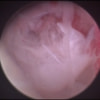

関節鏡検査を実施いたしました。関節鏡検査では、重度の滑膜炎および前十字靭帯の完全断裂が認められました。半月板に損傷は認められませんでした。

関節穿刺を行い、好中球はなく、少数のマクロファージや滑膜細胞が認められるました。膝蓋骨脱臼および前十字靭帯断裂による退行性の関節炎を疑い、関節鏡検査を実施いたしました。関節鏡検査では、重度の滑膜炎および前十字靭帯の完全断裂が認められました。内外側とも半月板に損傷は認められませんでした。